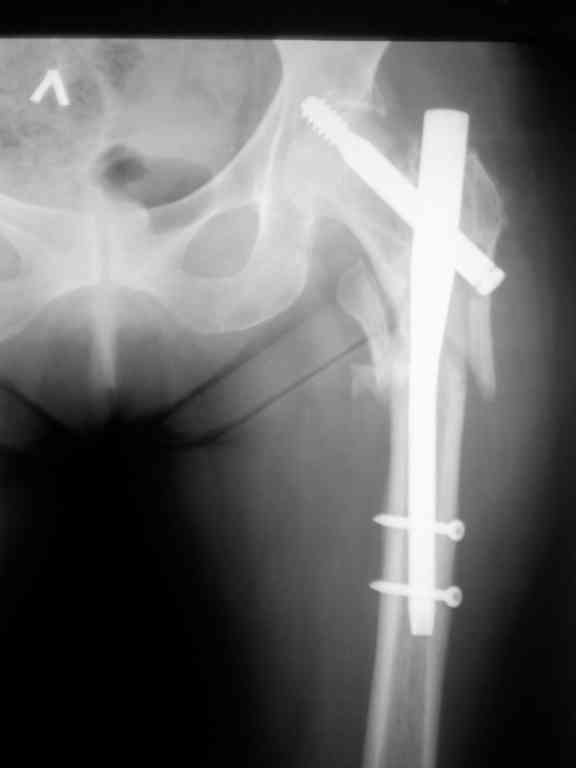

Перелом тут больше подвертельный. Нагрузка без торцевого упора на уровне перелома привела к телескопированию отломков на стержне. Ну и варус небольшой тоже свою лепту внес - если бы его не было, контактирующие латеральные стенки обоих отломков предотвратили бы укорочение, да и срослось бы за пару месяцев. А раз не срослось, упора отломков нет, более слабым местом оказались не нижние винты, а кость в головке и шейке. Так что надо было хотя бы удалить нижние винты до начала полной нагрузки.

На мой взгляд, причиной телескопирования явилось несоответствие диаметра гамма нэйл с диаметром канала подвертельного отдела бедра: обратите внимание на величину протрузии шеечного винта и величину медиализации дистального фрагмента - они одинаковы, смещение или телескопирование фрагментов происходило до того момента, пока гамма нэйл не упёрся в медиальный кортекс и образовалось пространство между латеральным

кортексом и латеральной поверхностью гвоздя.

Диаметр гаммы в диафизарной части ~11 мм. А диаметр канала, тем более у пожилых с остеопорозом, может быть мм 15. Даже рассверливать обычно не приходится, после формирования широкого канала в вертельной области можно сразу толкать гвоздь, он влетает, как карандаш в стакан. Так что соответствия диаметров не бывает никогда. Однако представленная ситуация случается далеко не каждый раз. Если гвоздь в центральном отломке входит чуть медиальнее верхушки вертела, и идет вдоль передне-латеральной стенки центрального отломка, то все будет хорошо.